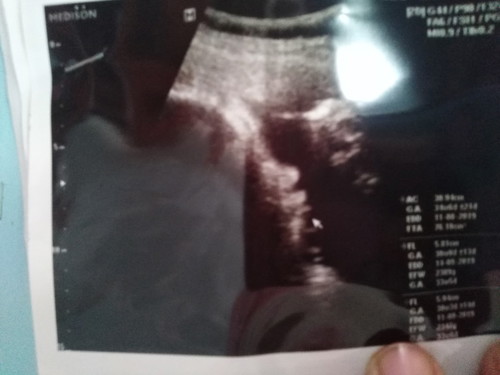

ตอนนี้ อายุครรภ์ 33 สัปดาห์แล้ว น้ำหนักลูก อยู๋ที่ 2300กรัม เล็กหรือใหญ่ไปค่ะ แล้วตอนนี้ ลูกยังไม่กลับหัว แม่ๆท่านไหนลูกกลับหัวกันแล้วบ้างค่ะ